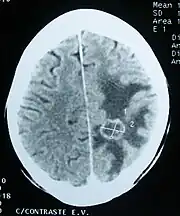

Imaging

Medical imaging plays a central role in the diagnosis of brain tumors. Early imaging methods – invasive and sometimes dangerous – such as pneumoencephalography and cerebral angiography have been abandoned in favor of non-invasive, high-resolution techniques, especially magnetic resonance imaging (MRI) and computed tomography (CT) scans,[38] though MRI is typically the reference standard used.[41] Neoplasms will often show as differently colored masses (also referred to as processes) in CT or MRI results.

- Benign brain tumors often show up as hypodense (darker than brain tissue) mass lesions on CT scans. On MRI, they appear either hypodense or isointense (same intensity as brain tissue) on T1-weighted scans, or hyperintense (brighter than brain tissue) on T2-weighted MRI, although the appearance is variable.

- Contrast agent uptake, sometimes in characteristic patterns, can be demonstrated on either CT or MRI scans in most malignant primary and metastatic brain tumors.

- Pressure areas where the brain tissue has been compressed by a tumor also appear hyperintense on T2-weighted scans and might indicate the presence of a diffuse neoplasm due to an unclear outline. Swelling around the tumor known as peritumoral edema can also show a similar result. This is because these tumors disrupt the normal functioning of the BBB and lead to an increase in its permeability.

More recently, advancements have been made to increase the utility of MRI in providing physiological data that can help to inform diagnosis and prognosis. MRI itself is sufficient in identifying the brain tumor’s location and morphology, but other types of MRI may be used on top of that, such as MRA, MRS, pMRI, fMRI, and DWI. These imaging techniques help doctors and surgeons to diagnose the type of tumor, to plan for surgery, and to assess treatment and radiation/chemotherapy.